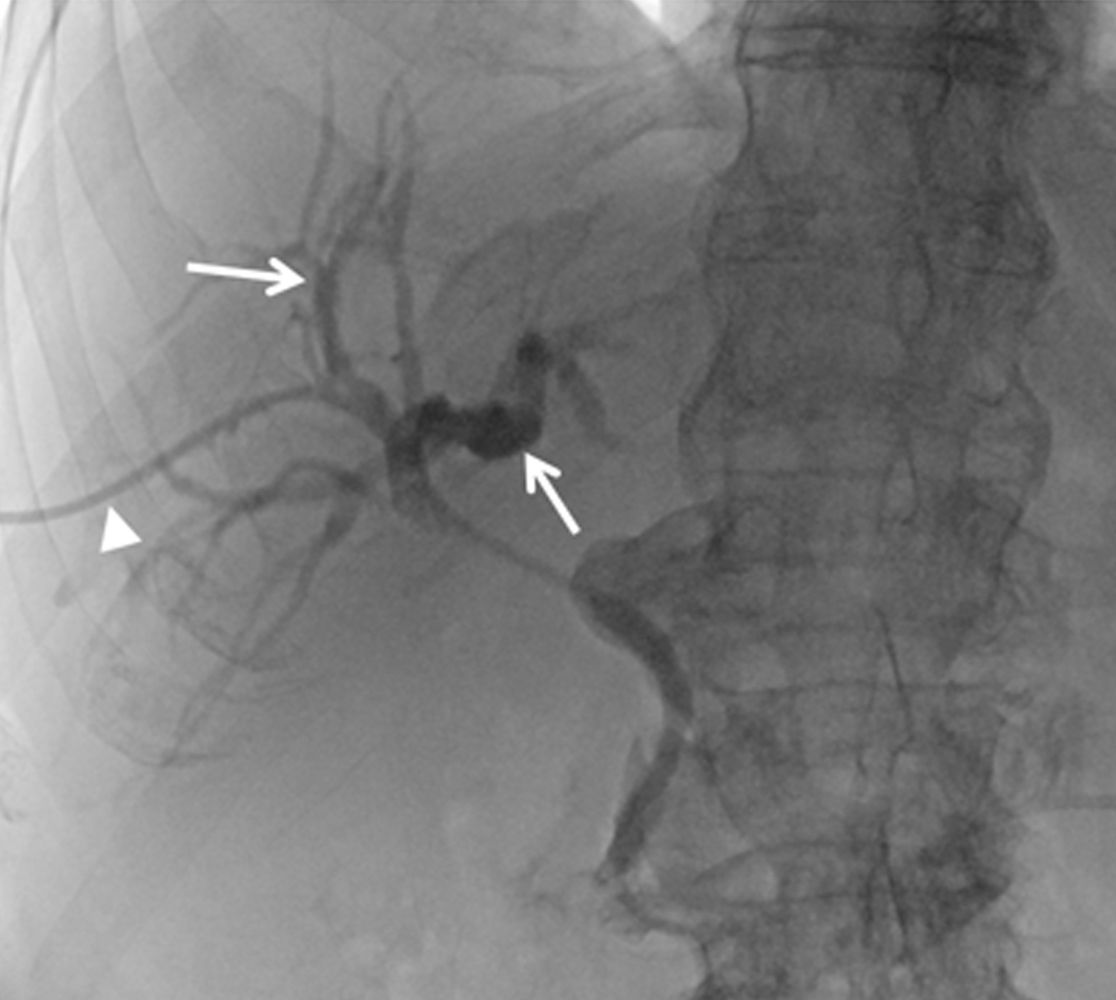

Darstellung der Gallenwege (Pfeile) über die einliegende Drainage (Pfeilkopf) in der Angiographie.

Bei der PTCD wird unter sonographischer und röntgenologischer Kontrolle von außen durch die Haut (perkutan), durch die Leber (transhepatisch), das Gallenwegs-System mit Kontrastmittel dargestellt (Cholangiographie). Anschließend ist es möglich, einen Katheter als Drainage einzubringen um so einen Abfluss gestauter Gallenwege zu gewährleisten. Ursächlich für einen gestörten Abfluss der Gallenwege können verschiedene gutartige oder bösartige Prozesse sein. Primäres Ziel der Therapie ist eine Entstauung der Gallenwege und idealerweise das Etablieren eines dauerhaften Abflusses in nach enteral (in den Darm) mit der Option, die PTCD im weiteren Verlauf wieder entfernen zu können.